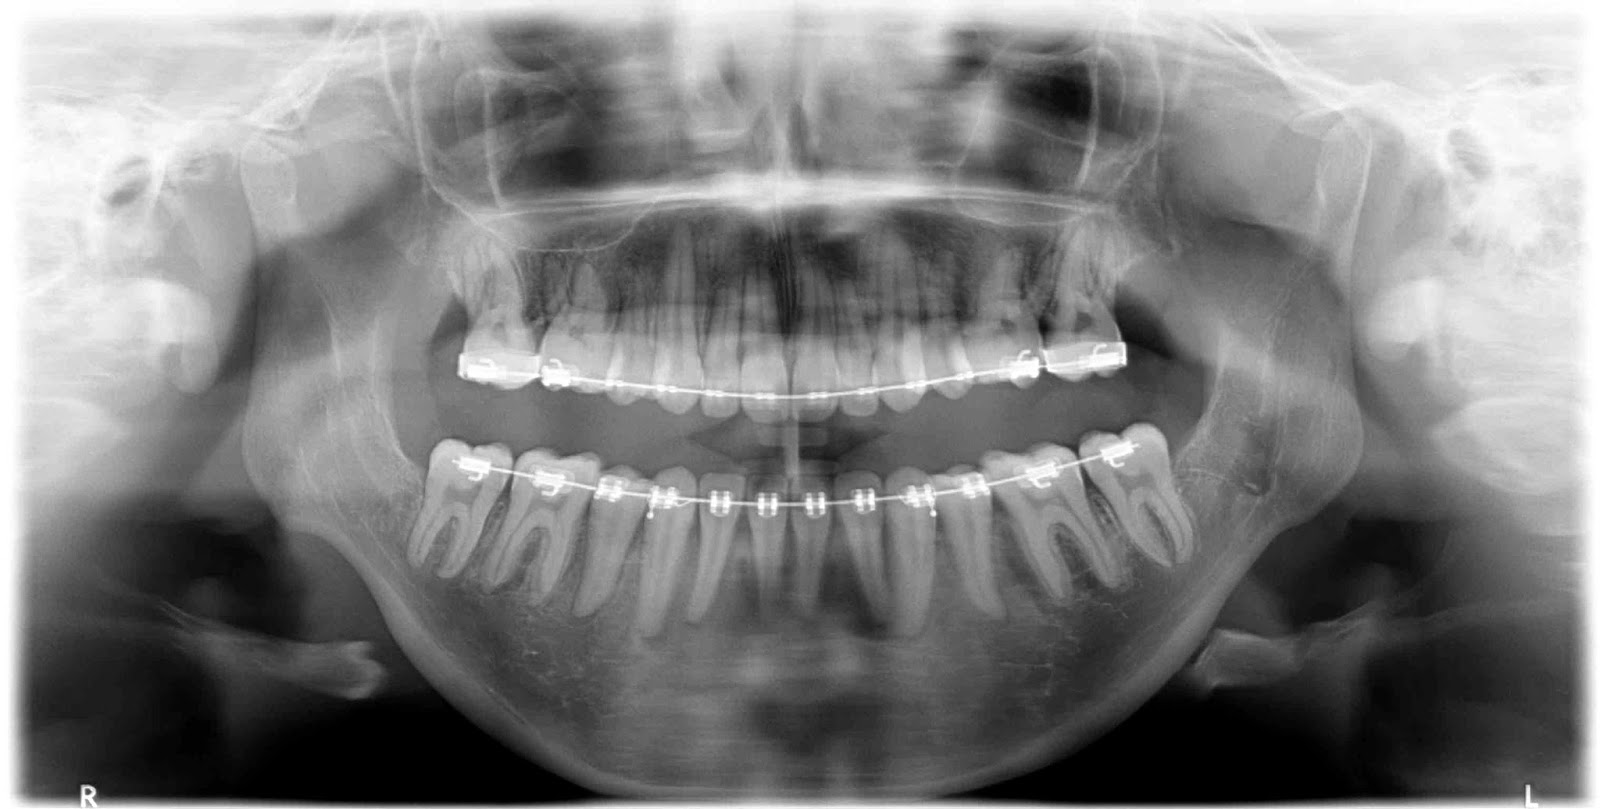

Double jaw surgery and chin reduction r/XRayPorn Double Jaw Surgery X Ray jaw surgery, also called orthognathic surgery, is surgery that helps align your upper jaw (maxilla) and lower jaw. You can see, quite clearly, the drastic change that took place on the operating. Learn more about how this surgery works and how we can help. Most people undergo jaw surgery to treat. Jaw surgery, or orthognathic surgery, corrects jaw problems. Double Jaw Surgery X Ray.

In Depth What is Orthognathic Surgery and Would You Benefit From it? — eLINE Orthodontics Double Jaw Surgery X Ray They do a decent job of. Most people undergo jaw surgery to treat. You can see, quite clearly, the drastic change that took place on the operating. what is double jaw surgery? Learn more about how this surgery works and how we can help. mouth breathing, dry mouth, jaw pain, difficulty chewing, and an inability to bite led. Double Jaw Surgery X Ray.

Before And After Double Jaw Surgery Seoul Guide Medical Double Jaw Surgery X Ray what is double jaw surgery? You can see, quite clearly, the drastic change that took place on the operating. Jaw surgery, or orthognathic surgery, corrects jaw problems and related conditions. Most people undergo jaw surgery to treat. jaw surgery, also called orthognathic surgery, is surgery that helps align your upper jaw (maxilla) and lower jaw. mouth breathing,. Double Jaw Surgery X Ray.

Jaw Surgery in Merrillville, Valparaiso, and Michigan City Double Jaw Surgery X Ray They do a decent job of. mouth breathing, dry mouth, jaw pain, difficulty chewing, and an inability to bite led me to double jaw surgery. Jaw surgery, or orthognathic surgery, corrects jaw problems and related conditions. jaw surgery, also called orthognathic surgery, is surgery that helps align your upper jaw (maxilla) and lower jaw. double jaw surgery. Double Jaw Surgery X Ray.

Getting everything straight. My double jaw surgery Xrays Double Jaw Surgery X Ray Learn more about how this surgery works and how we can help. what is double jaw surgery? mouth breathing, dry mouth, jaw pain, difficulty chewing, and an inability to bite led me to double jaw surgery. double jaw surgery corrects both the upper and lower jaw at the same time. Jaw surgery, or orthognathic surgery, corrects jaw. Double Jaw Surgery X Ray.